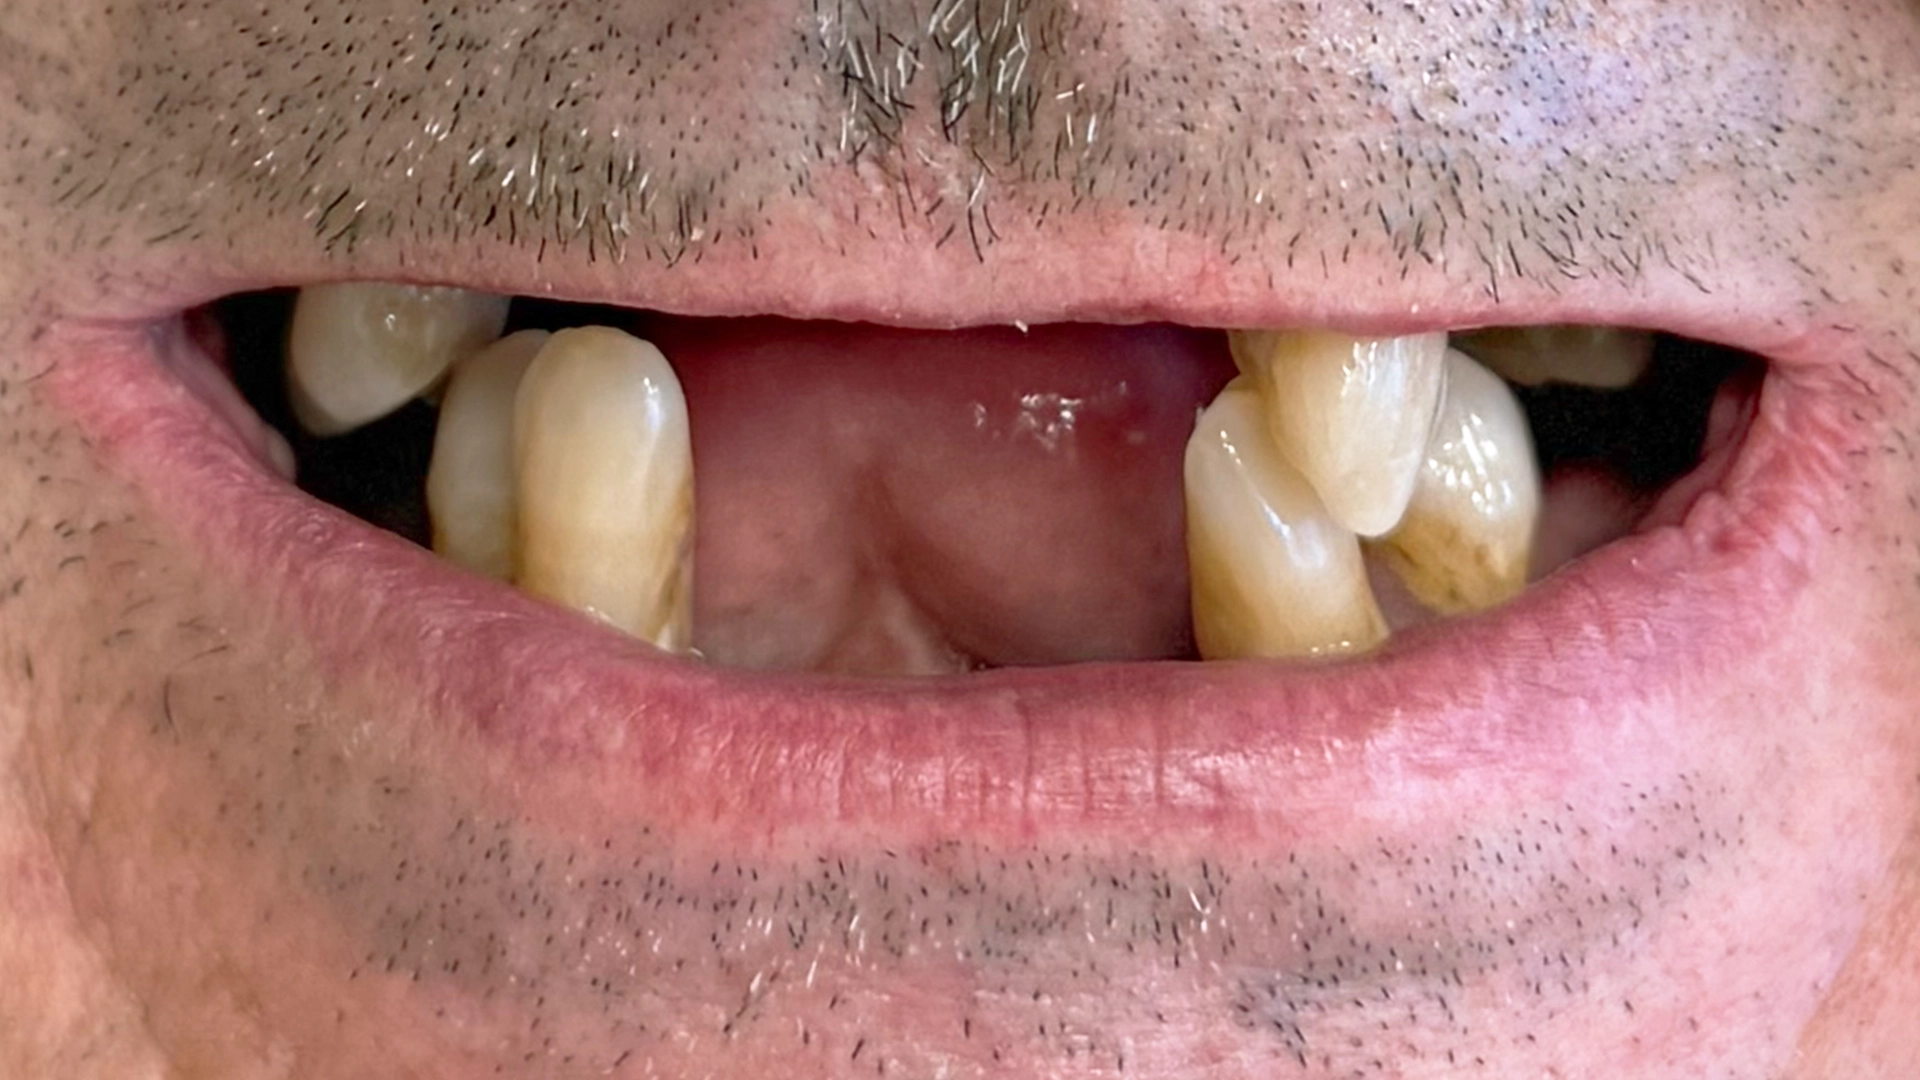

If you’re reading this, you’ve probably been living with a missing tooth—or several—for longer than you originally expected. You may have received different opinions from different dentists. You may be unsure what implant treatment actually involves, how long it takes, or whether the final result will truly feel like your own teeth.

Many patients assume they will leave the clinic without teeth on surgery day.

You leave the clinic the same day with a functional, natural‑looking tooth.

Unless you choose to mention it, no one will know you’ve had surgery.

Many patients describe this moment as quietly emotional—not dramatic, but deeply relieving.

After months or years of adapting to a gap, a removable solution, or a restoration that never felt right, you simply stop thinking about the tooth.